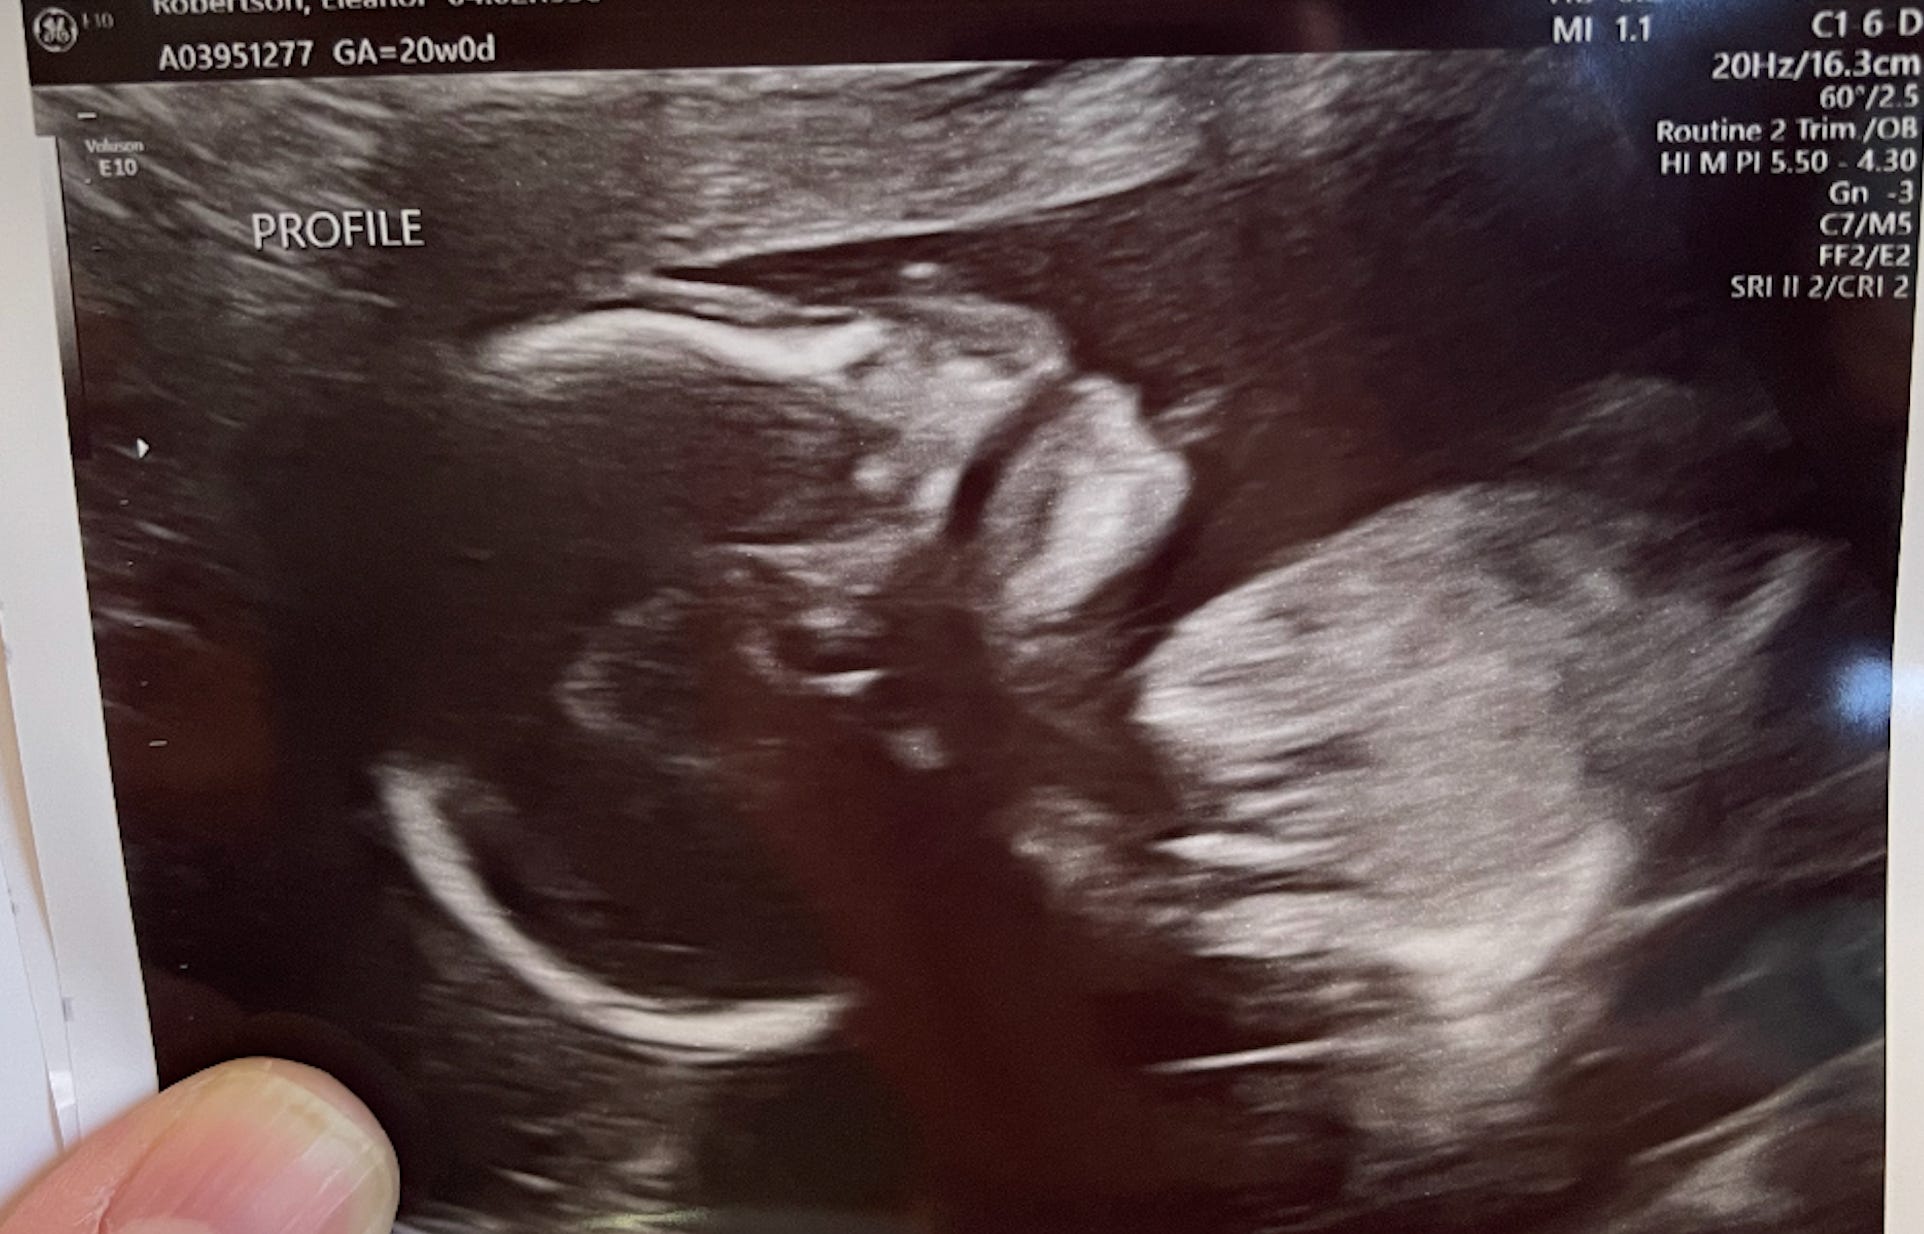

20 Weeks

Yesterday I saw my unborn son’s long bones on an ultrasound. Happily, they all seem to be there: your tibias, fibias, femurs, and so on, stark white against the television-static grey of the sonographic background. I’ve seen these parts of his body in the same way before, but not since the bones actually calcified. At the previous ultrasound they were visible, but rendered in a light misty colour, as though the contrast setting in his body was still being turned up. Yesterday, as the sonographer chased him around my womb trying to get a clear image of his arms (UPPER.LIMBS in the allcaps sonographic annotation terminology), she alighted on his radius and ulna, pointy little bones that he is already using to fling his arms around inside me. She froze the live video and zoomed in on these two complementary forearm bones. This image generated an immediate and intense memory of seeing a seagull swallow a whole, chewed-up chicken wing on the playground of my primary school about twenty years ago. I was upset by this, and it was the only time during the session that I felt like I might cry.

These symptoms have essentially ground my social life to a halt, increasing the strange, unreal, lonely qualities of this period. I’ve been to a couple of parties and weddings, but I’m always thinking I’m so tired, have I yawned too much already, when is it acceptable for me to leave, and so on. I’ve spent a lot of time alone with my son, agonising over what to name him, imagining what he will be like and what I will be like as his mother, hoping he inherits the features I find so attractive and endearing about his father. But ultimately, all of this solitary contemplation feels a bit insubstantial; he feels the most real when other people acknowledge that he is there, especially if I perceive their acknowledgement as somehow incorrect, giving me something to assert, even if I don’t actually say anything. At the ultrasound where I saw his bones, the sonographer insisted on using the due date derived from my last menstrual period, even though by my calculations, and by every other ultrasound I’ve had, this is five days too late; at the end of the ultrasound she then told me he was measuring five days ahead. Of course he is measuring five days ahead you dumb bitch, I thought to myself. I told you already, he’s five days older than you think he is.